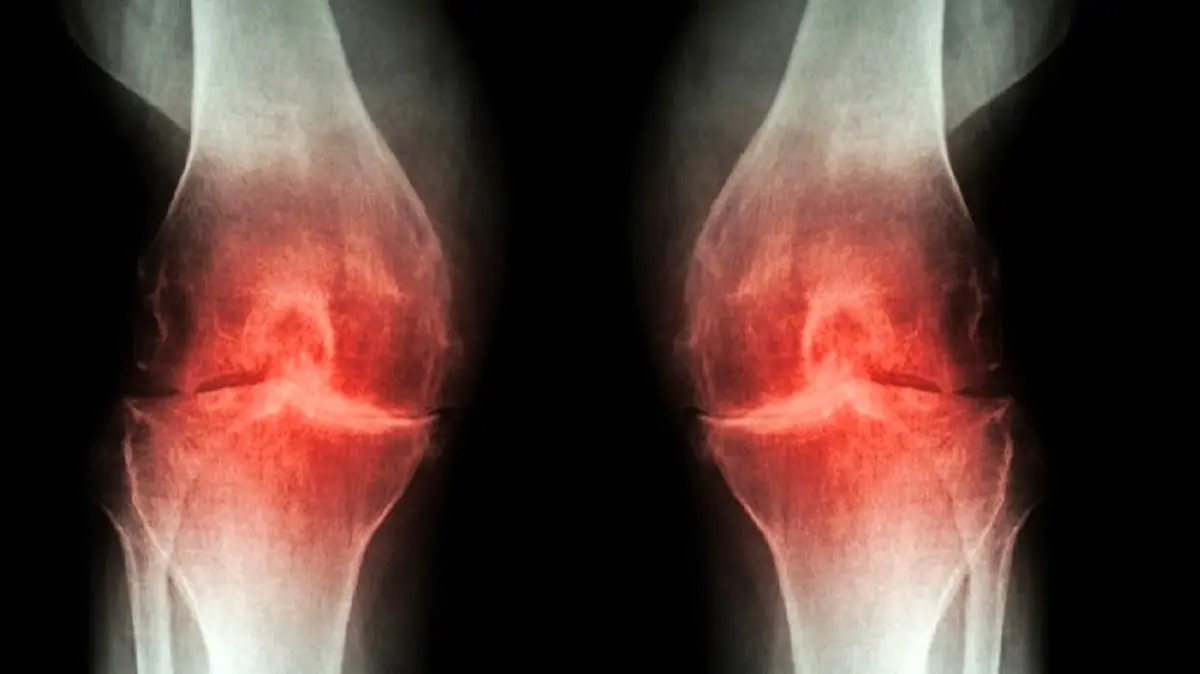

درمان دردهای مفصلی در طب سنتی

دردهای مفصلی بسیاری از افراد را درگیر کرده است. دردهای مفصلی موجب خستگی زودرس در طول روز می شود. مهم ترین عامل در دردهای مفصلی تحرک نداشتن و ثابت برای مدت طولانی در یک جا نشستن است. درمان دردهای مفصلی را باید جدی گرفت تا کهنه نشود و مشکلات حاد برای فرد ایجاد نکند. طب سنتی راهکارهایی را برای درمان دردهای مفصلی ارائه داده است.

علیرضا یارقلی متخصص طب سنتی درباره این موضوع که علائم بیماری‌های مفصلی در تابستان با باد کولر و پنکه افزایش می‌یابد، گفت: زندگی ماشینی باعث شده اتاق‌های ما در تابستان سردتر از زمستان باشد. زندگی ماشینی و بدن‌های پُر و بد انباشته باعث شده تا در تابستان زیر کولر و پنکه باشیم و طاقت گرما نداشته باشیم و این امر موجب سردی اولیه مزاج بدن می‌شود و شاهد درد و کوفتگی مفاصل هستیم در فاز‌های بعدی دچار ریزش ماده و ورم مفاصل هم می‌شویم که خطرناک‌تر است.

این متخصص طب سنتی ادامه داد: در یک خانه افرادی با مزاج‌های مختلف زندگی می‌کنند هرچه سن بالا می‌رود مزاج به سمت سردشدن می‌رود. افراد زیر ۲۵ سال مزاج گرم و‌ تر دارند و تا ۴۰ سال گرم و خشک و تا ۶۰ سالگی مزاج، سرد وخشک می‌شود. بعد از این سن رطوبتی به بدن اضافه می‌شود که موجب دست و پا درد افراد مسن می‌گردد و با سرما فرآیند‌های التهابی روماتیسم و دردی مفاصل به آن اضافه می‌شود و به دلیل اضافه وزن و کاهش متابولیسم چرخه‌ای از بیماری‌ها به وجود می‌آید.